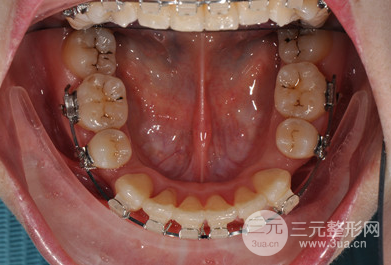

在做牙齒正畸這段時間里,一直都堅持飲食清淡和清潔工作,不能過度咀嚼,所以在著兩年多的堅持下還是有很明X的改良的。

矯正期間沒個一段時間就要回醫(yī)院做復(fù)查和更換牙套,好在醫(yī)生的技術(shù)比較好,牙齒矯正比較爭氣,現(xiàn)在想過很滿意,不僅沒有凸嘴,牙齒也很整齊,現(xiàn)在已經(jīng)取了牙套之后可以隨意吃吃喝喝了,這兩天沒有白堅持。